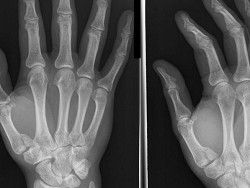

Американские ученые сумели создать уникальные наночастицы, которые помогут медикам в лечении переломов. Планируется, что они существенно ускорят восстановление костей. Эта новинка кажется биологам очень перспективной.

Наночастицы, изобретенные учеными, смогут доставлять в нужные места молекулы, которые стимулируют деление клеток организма. А это значит, что ликвидация повреждений сможет происходить намного быстрее, чем раньше. Кроме того, планируется использовать их для других задач. Например, их можно будет задействовать в ходе операций на костях или применять для лечения кариеса. В таком случае, очень скоро пломбы могут больше не понадобиться человечеству – зубы смогут самовосстанавливаться.